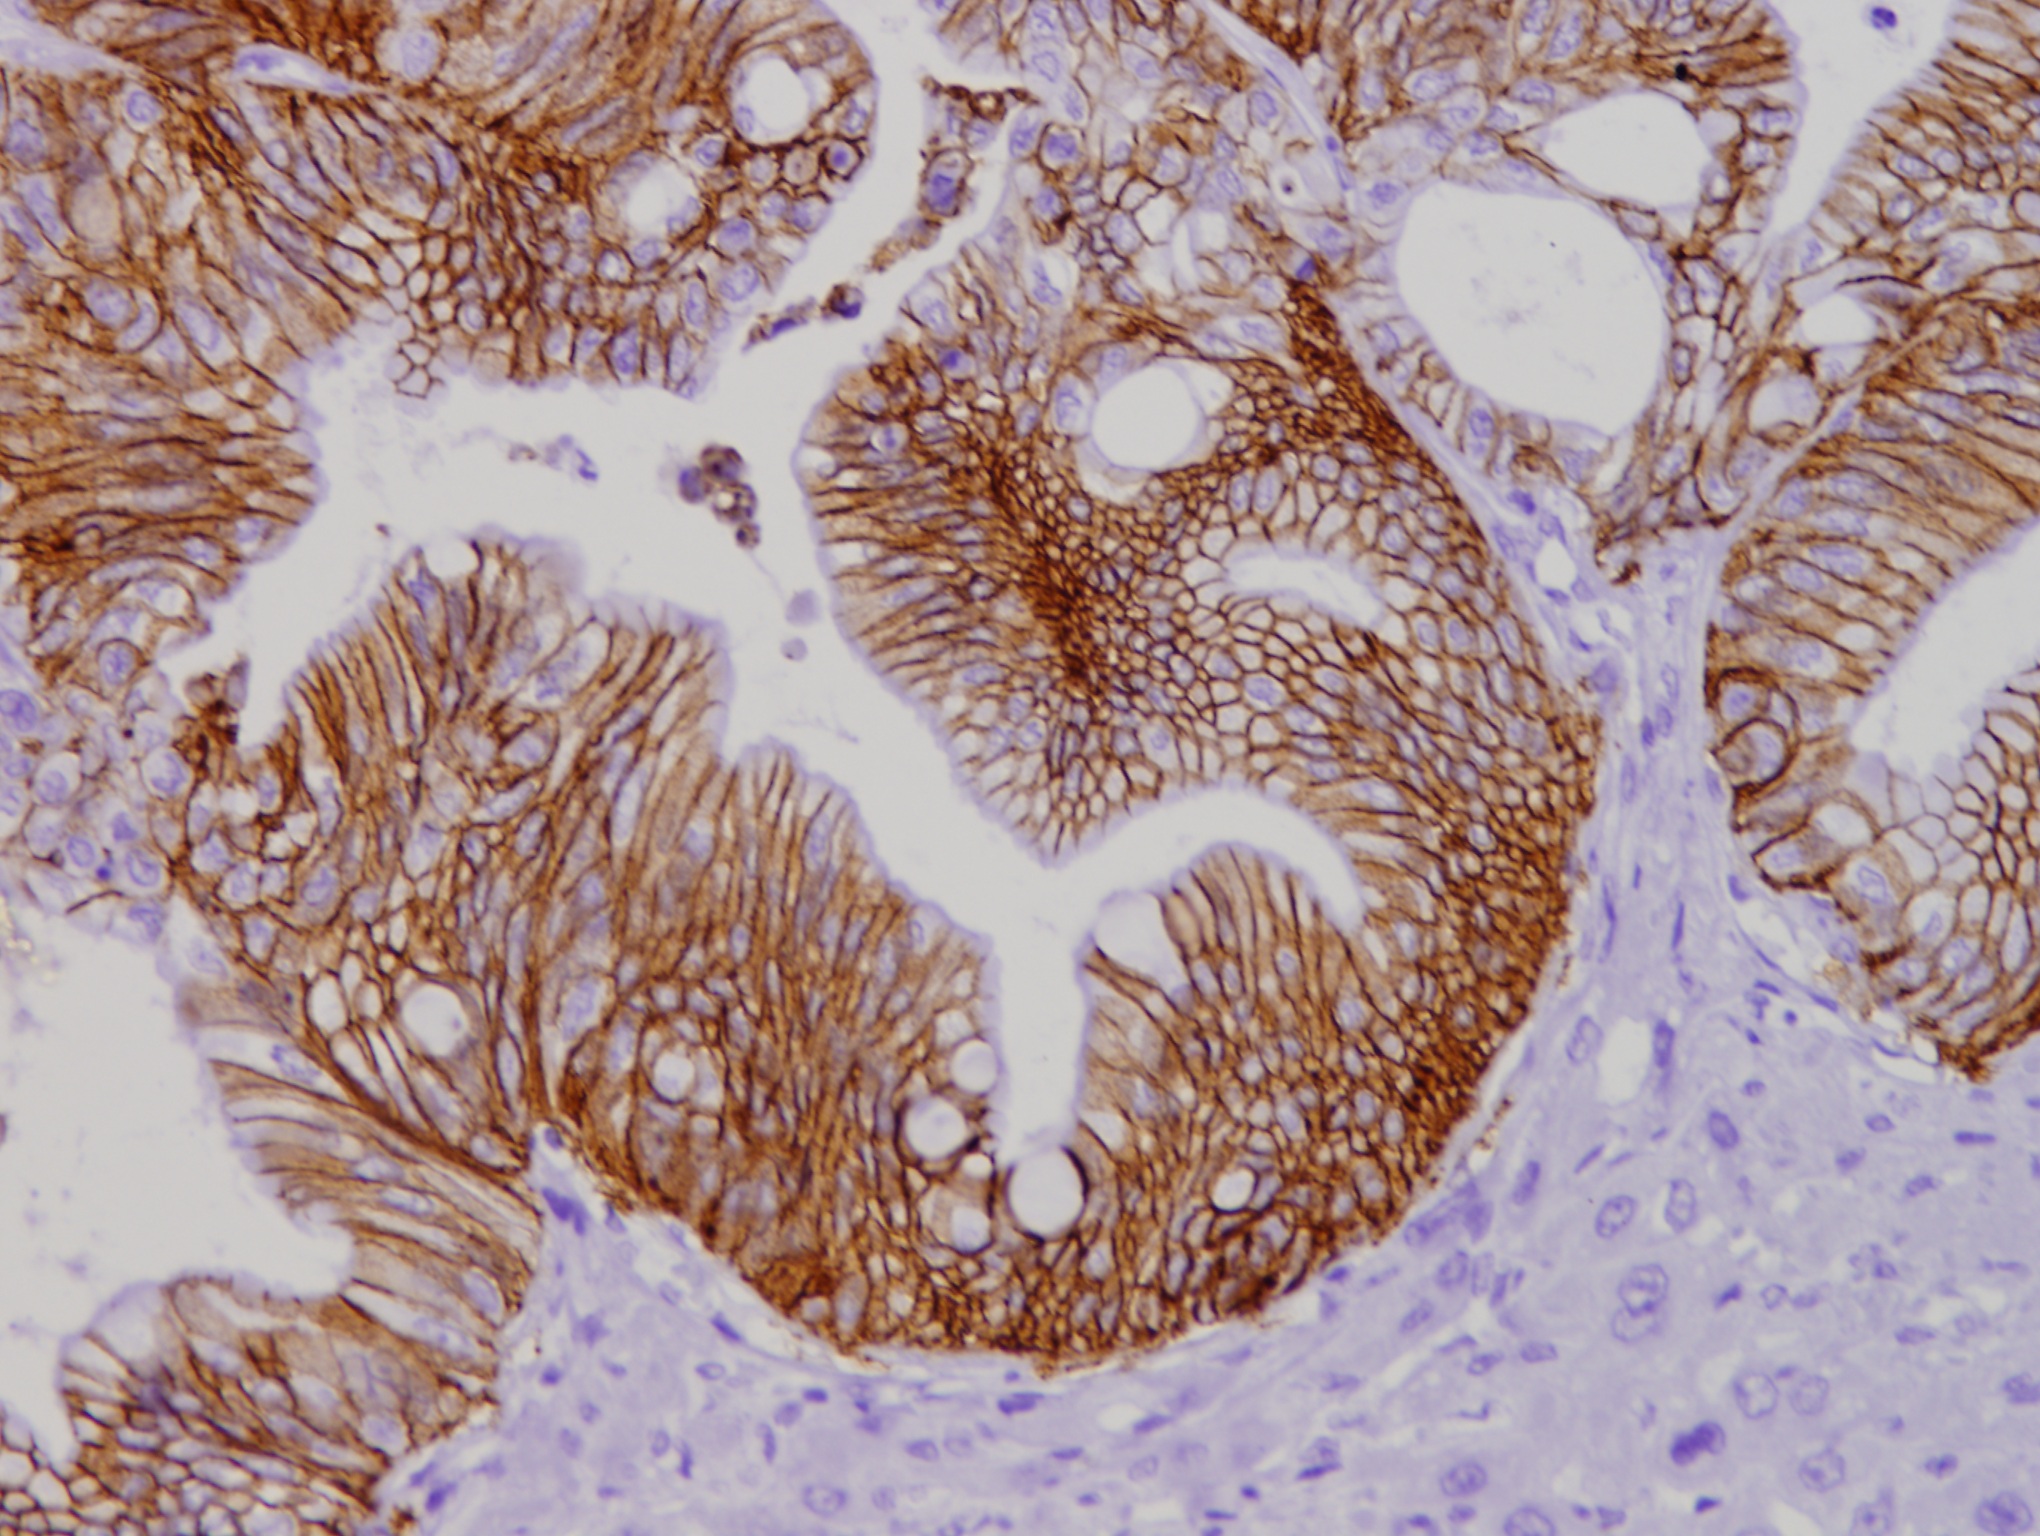

El estudio se ha llevado a cabo utilizando organoides derivados de células de pacientes con cáncer de colon, a los cuales se eliminó la quinasa IKKα. Después, en modelos preclínicos en ratones, los investigadores demostraron que "hay una subpoblación específica de células tumorales, caracterizada por uniones celulares especialmente robustas, que es la responsable de generar metástasis en el hígado", apunta el Dr. Espinosa. Esta población celular estaba claramente enriquecida en ausencia de IKKα, hecho que se explica porque los tumores deficientes en esta proteína presentaban más capacidad metastática. De manera paradójica, a pesar de que esta proteína había sido descrita previamente como promotora tumoral en otros contextos, el nuevo trabajo revela que también puede actuar como supresor de la metástasis en el cáncer de colon.

Los investigadores también han comprobado cómo, inhibiendo determinadas proteínas implicadas en estas uniones celulares, como es el caso de la claudina 2, se reduce significativamente su capacidad para producir metástasis.